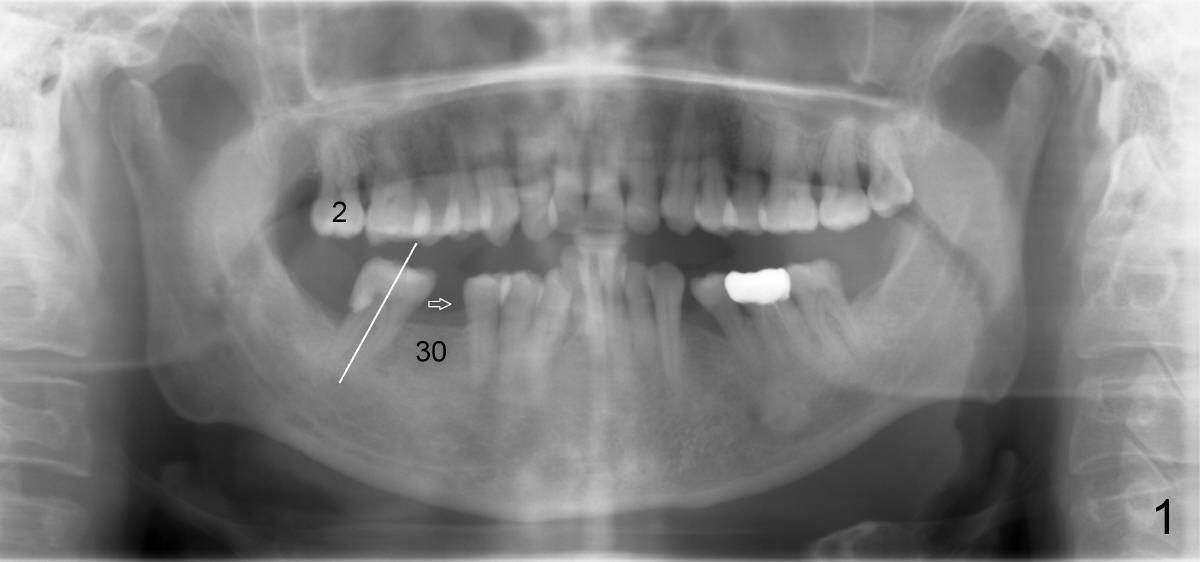

A 50-year-old man has lost the lower right 1st molar for several years (Fig.1: 30). The 2nd molar has shifted (arrow) and inclined (white line) mesially. It does not appear to occlude with the tooth #2 in this panoramic X-ray. It is planned to place an implant at the site of #30 and after osteointegration to use it as an anchorage to upright and distalize the tooth #31. Four and a half months after placement of a Tatum tapered implant (6x17 mm), a 5 mm 10 degree unipost ((short) abutment) is placed and prepared for temporary crown (Fig.2: A). Severe cross bite (overjet) is noted between the teeth #2 and 31. It is due to combination of the lingual inclination of the tooth #31 (Fig.3 (mirror view) arrow) and the buccal displacement of the tooth #2 (Fig.4 mirror image).